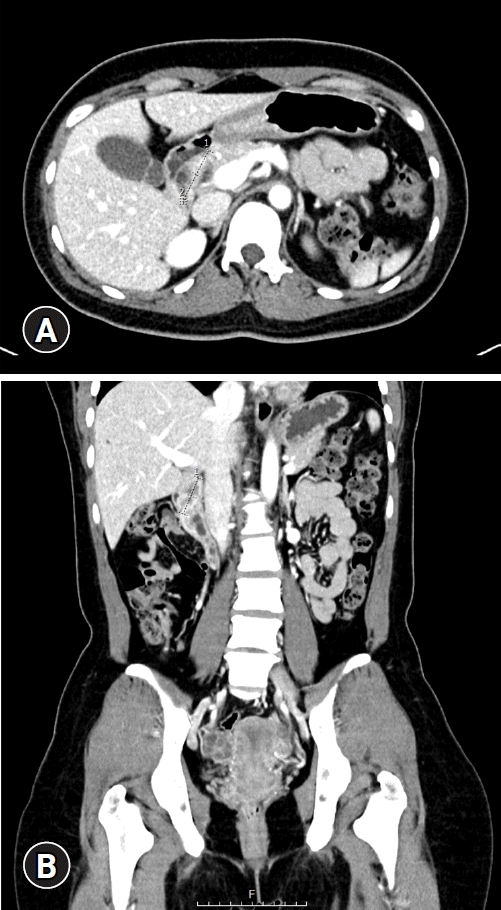

Fig. 1.

Contrast-enhanced abdominal pelvis computed tomography scan findings. (A, B) Axial and coronal images revealed a large polypoid mass in the duodenal bulb extending to the 2nd portion, measuring 4 cm in size.